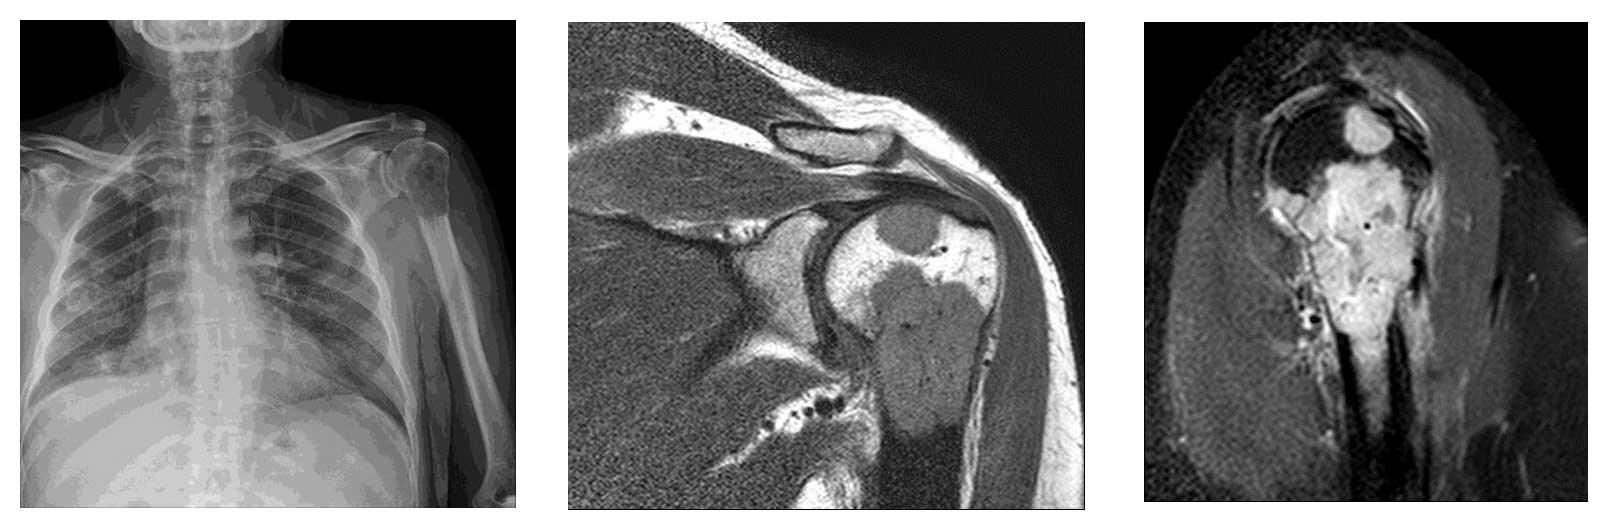

Ameliyat Öncesi: Röntgende humerus üst uçta kemik yıkımı, MR’da tümörün kemik dışına çıktığı görülmekte.